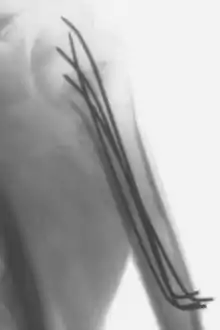

كسر في العضد الأيسر مثبت بأربعة أسلاك كيرشنر

أسلاك كيرشنر (بالإنجليزية: Kirschner wires) أو أسلاك ك (بالإنجليزية: K wires) أو السفافيد (بالإنجليزية: pins) هي أسلاك مدببة وملساء مصنوعة من صلب لا يصدأ تستخدم كثيراً في جراحات العظام، وبعض العمليات الجراحية البشرية والبيطرية الأخرى.[1][2][3] أدخلها مارتن كيرشنر سنة 1909 وما زالت مستخدمة بمقاساتها المختلفة إلى اليوم. تستخدم أسلاك كيرشنر لتثبيت شظايا العظم المكسور معاً وكذلك تستخدم في عمليات الجر الهيكلي، ويتم إدخال الأسلاك في العظم باستخدام شنيور يدوي أو كهربي. تشكل أسلاك كيرشنر أيضاً جزءاً أساسياً من جهاز إليزاروف.